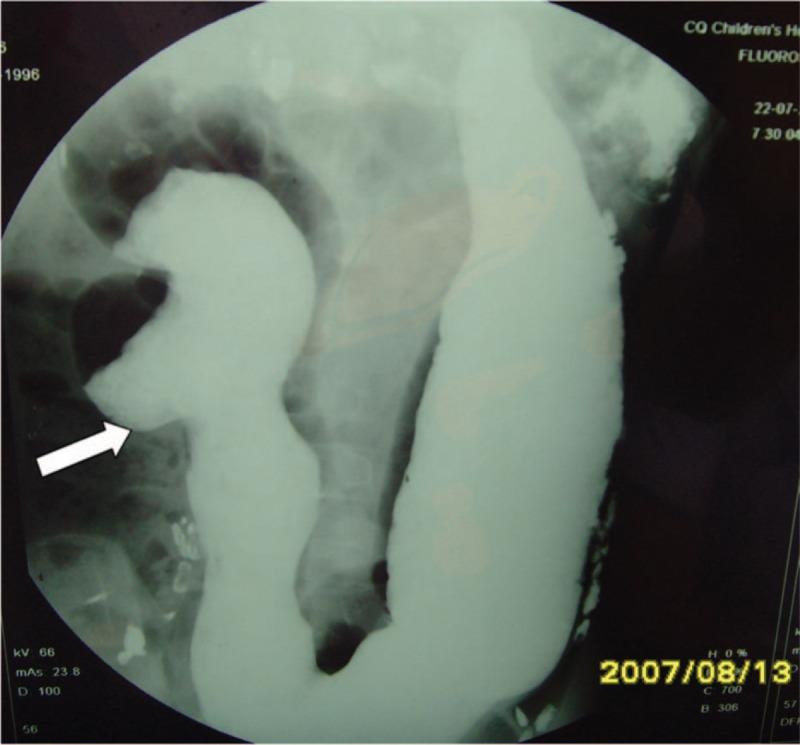

Due to the various presentations of gastrointestinal tract duplications (GTD), diagnosing and management for this disease might be varied and difficult. We intend to improve the experiences for these difficult, in terms of the clinical presentations, diagnostic investigations, management.We reviewed recent literature and retrospectively analyzed 72 pediatric patients with enteric duplication. Diagnosis was confirmed by surgery and pathological examination for imaging characteristics and clinical and pathological features.The ages of patients ranged from one month to 12.5 years. The clinical presentations of the patients included 57 cases with abdominal pain, followed with nausea or vomiting, abdominal distension, etc. All of the patients were diagnosed by ultrasonography, and most of them presented as intra-abdominal cystic masses. Four cases were diagnosed with the cysts other than GTDs, like, mesenteric cyst, chledochal cyst and abscess, and so on. Computed tomography was performed on 65 patients. X-rays and barium meal showed the outline of the cyst structure, with intestinal displacement due to the pressure from the cyst. Among the 72 cases of enteric duplication, 45 were located with ileocecal area, 41 were ileal and 8 were colonic duplications.Enteric duplication is very rare in children and is prone to misdiagnosis. The preoperative diagnosis of enteric duplication can be improved through comprehensive analysis of various imaging exams and closely related clinical presentations.

由于胃肠道重复畸形(GTD)的表现多样,该病的诊断和治疗可能存在差异且具有挑战性。我们旨在从临床表现、诊断检查、治疗等方面改善对这些疑难病症的诊治经验。我们回顾了近期文献,并对72例小儿肠重复畸形患者进行了回顾性分析。通过手术及病理检查,依据影像学特征以及临床和病理特征确诊。患者年龄从1个月至12.5岁不等。患者的临床表现包括57例腹痛,随后伴有恶心或呕吐、腹胀等。所有患者均通过超声检查确诊,大多数表现为腹腔内囊性肿块。4例被诊断为非GTD的囊肿,如肠系膜囊肿、胆总管囊肿和脓肿等。65例患者进行了计算机断层扫描。X线和钡餐显示了囊肿结构的轮廓,由于囊肿的压迫导致肠管移位。在72例肠重复畸形病例中,45例位于回盲部,41例为回肠重复畸形,8例为结肠重复畸形。肠重复畸形在儿童中非常罕见,且容易误诊。通过综合分析各种影像学检查和密切相关的临床表现,可以提高肠重复畸形的术前诊断率。